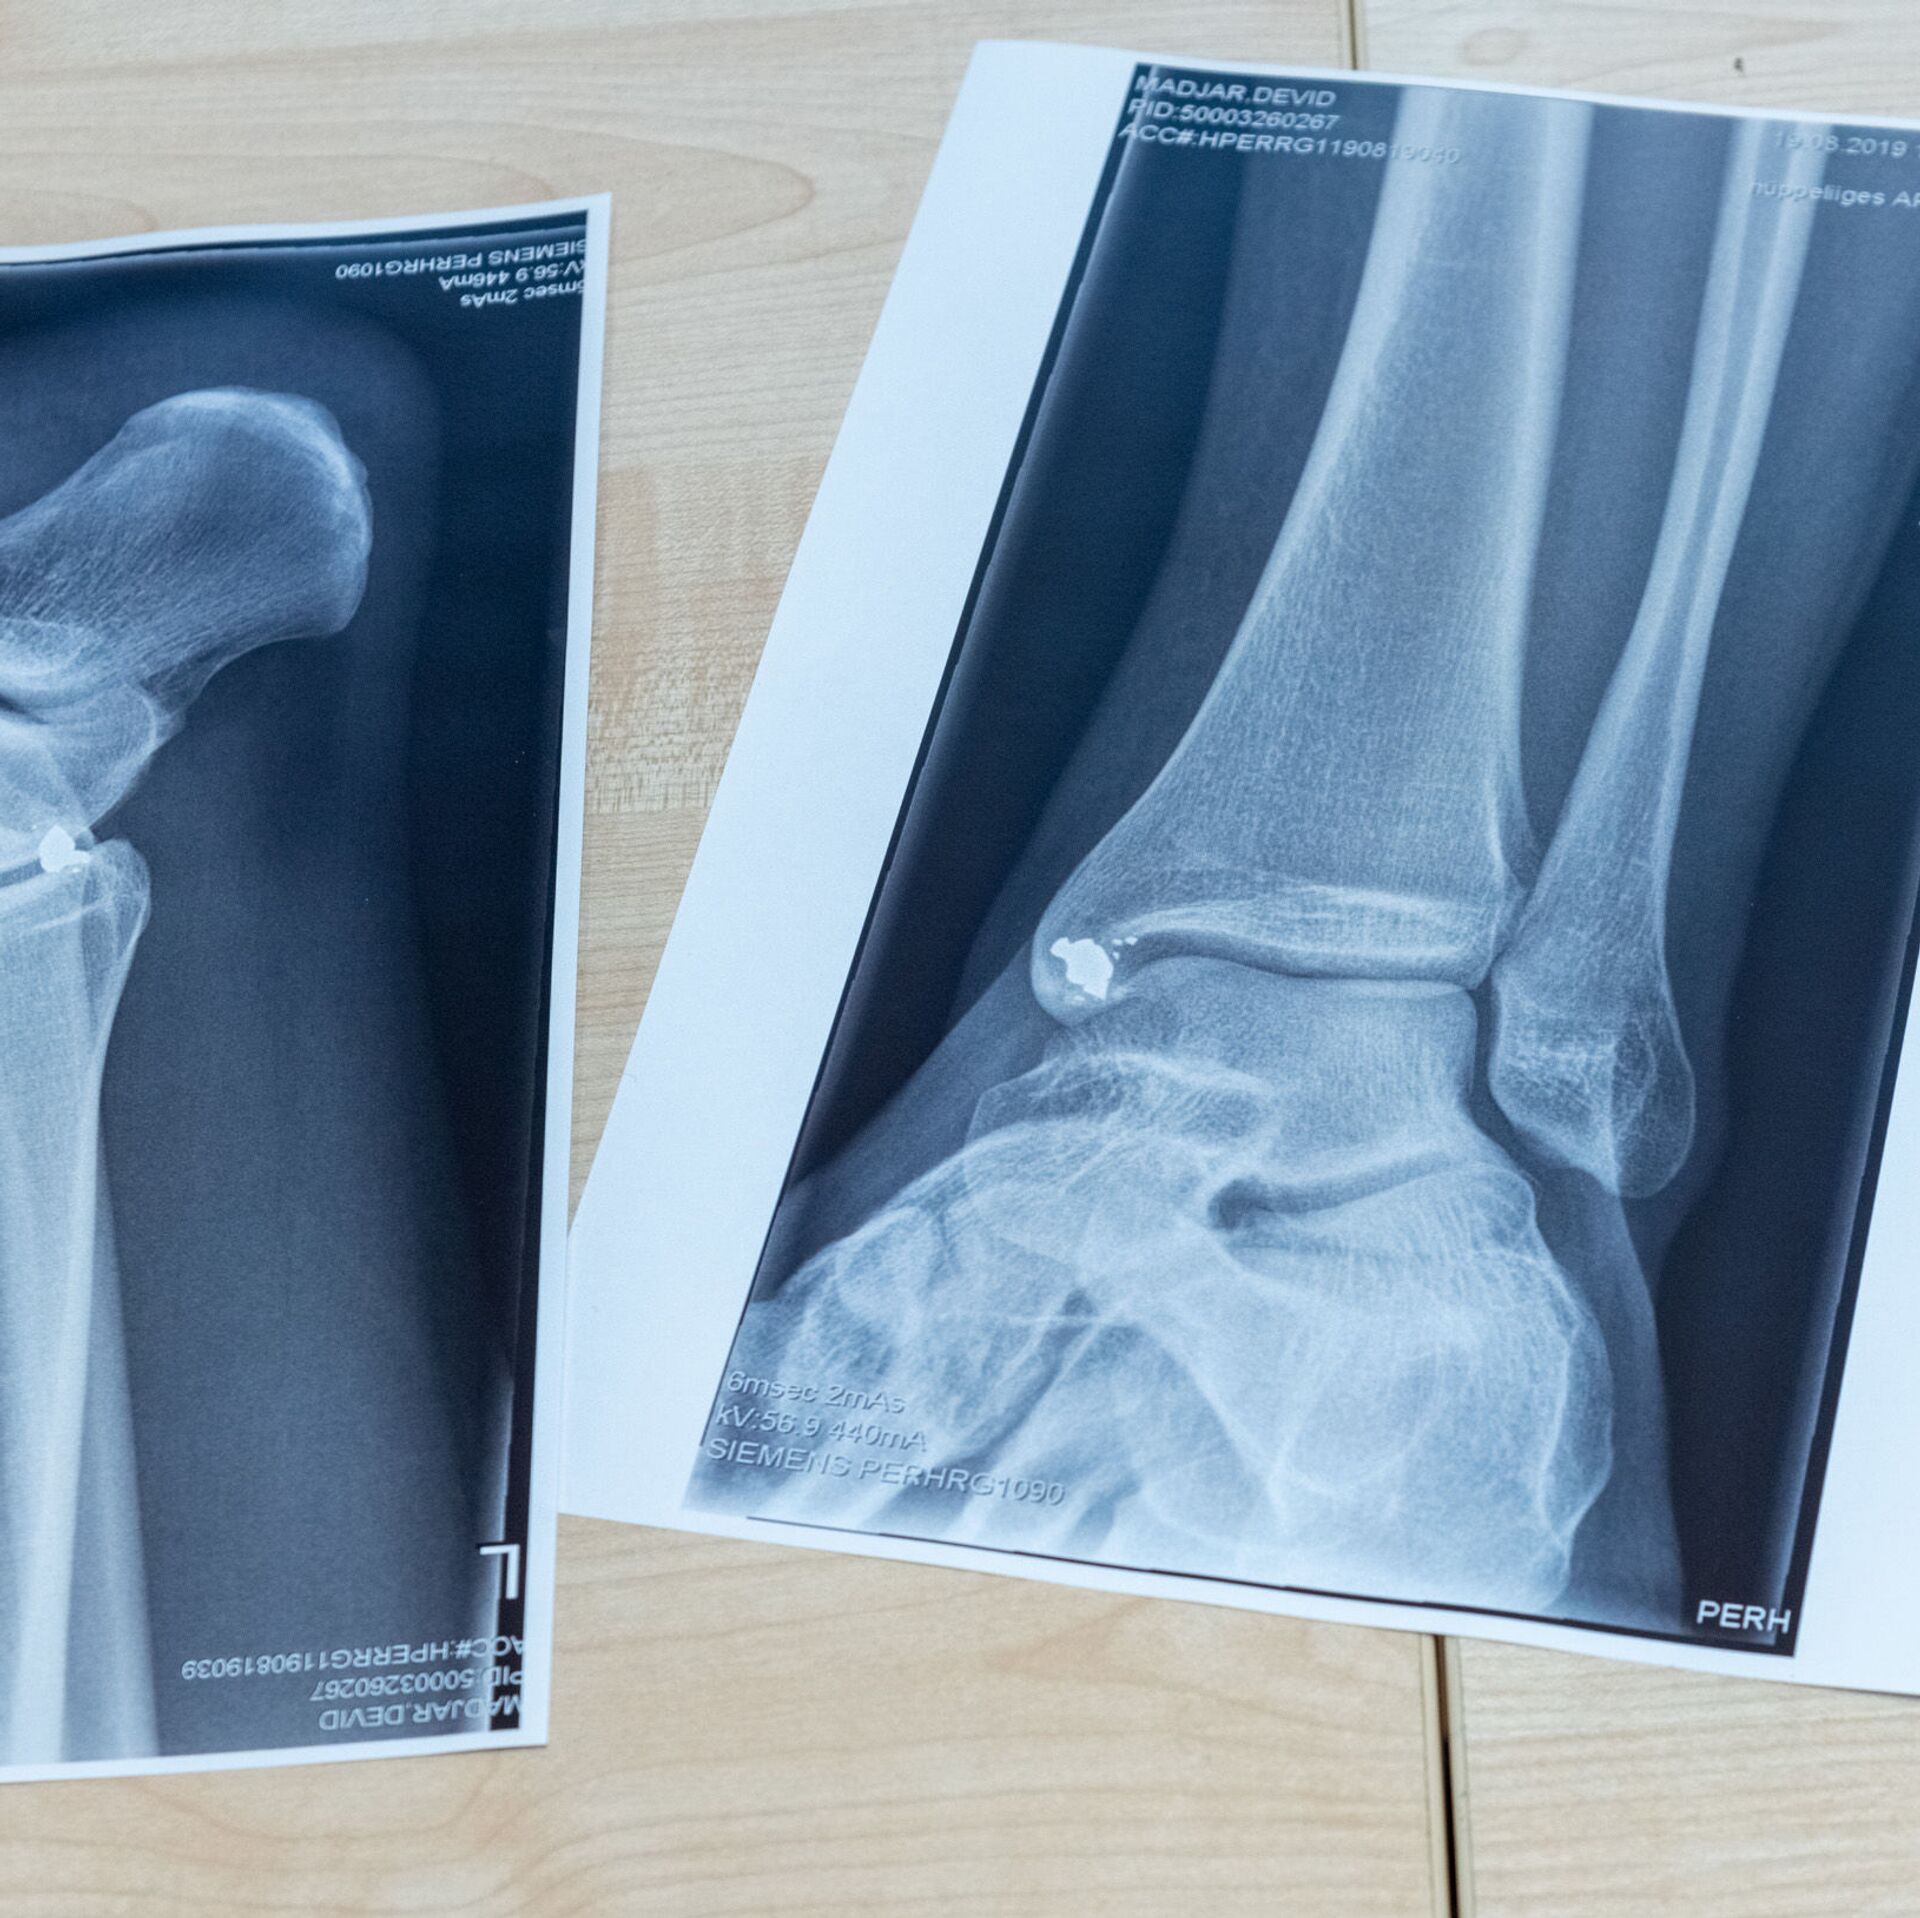

РИГА, 17 апр - Sputnik. В феврале этого года Екабпилсская больница получила жалобы на некачественную работу двух врачей-травматологов и приостановила работу отделения травматологии. Сейчас экстренную помощь пациентам оказывают помощники врачей или хирурги, а в более сложных случаях людей переводят в другие стационары - чаще всего в Мадону.

Больница объявила набор сразу на несколько вакансий: заведующего отделением травматологии, травматолога, ортопеда и дежурного травматолога. Медикам предлагают около шести тысяч евро брутто, а также возможность работать на неполную ставку. Но желающих пока нет.

Как отметил заместитель председателя думы Екабпилсского края по вопросам здравоохранения Айварс Ванагс, поиск травматологов напоминает "поиск иголки в стоге сена". Единственный кандидат хотел зарплату в 15 тысяч евро.

Если в течение ближайших двух месяцев специалистов найти не удастся, местные власти намерены начать переговоры с министерством здравоохранения о дальнейших шагах. Один из возможных сценариев - полное закрытие отделения до появления новых врачей.